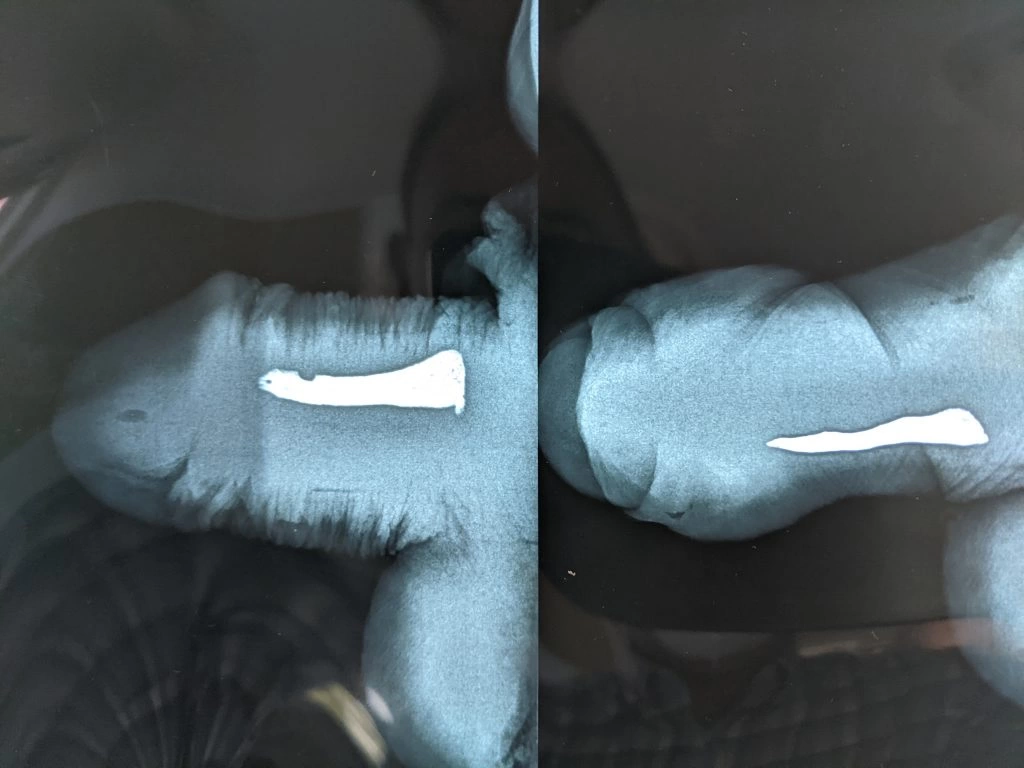

Na sequência de fotos abaixo, as imagens ecográficas mostram a evolução de uma placa de Peyronie em um paciente que realizou aplicações de verapamil:

Início do tratamento…

…terceira semana após o início das aplicações…

…final do tratamento (sexta semana).